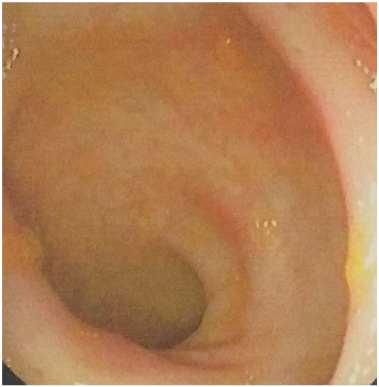

The isapgoal husk was given to the patient 2 teaspoonful twice daily in fresh yoghurt. The patient was given clinidium bromide thrice daily for relief of tenesmus. The patient was given sucralfate enema 30ml dissolved in equal quantity of water was given thrice daily. The prednislone enema was given twice daily alternating with sucralfate enema. These two enemas were given for one week. The sucralfate enema was continued for further two weeks. The biofeedback therapy was advised. The patient improved dramatically with all symptoms disappeared in these three weeks. Long term follow up treatment advised was isapgoal husk 2 teaspoonfuls in fresh yoghurt daily. One year follow up this patient has no symptoms and no ulcer in rectum (Figure 2).

Figure 2 Endoscopic view of healed ulcers.